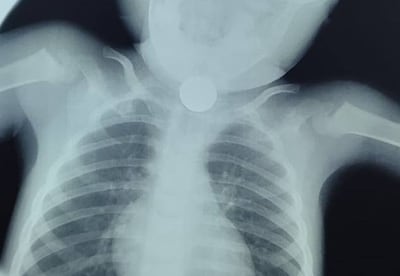

Recientemente, dos niños -una de nueve años y otro de tres años- fueron intervenidos en el Ineram luego de haber tragado monedas. Los procedimientos fueron realizados por el Dr. Carlos Morínigo, según él mismo dio a conocer.

Del esófago del pequeño se había retirado una moneda de G. 500, mientras que de la niña, una de G. 1.000.